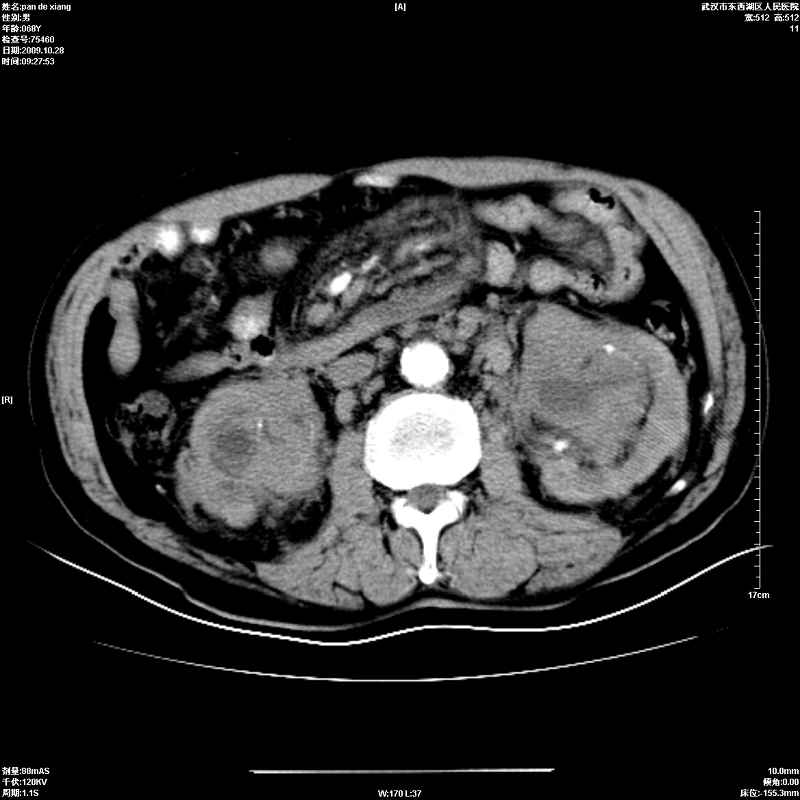

以下是引用杀毒软件在2009-10-28 20:41:00的发言:[br]结合临床考虑---白血病双肾改变或淋巴瘤。

以下是引用zxl51642在2009-10-29 9:59:00的发言:[br]结合临床“单克隆免疫球蛋白血症”,考虑双肾为继发损害并肾功能不全(尿中大量igg及少量iga、igm等大分子免疫球蛋白滤出所致继发损害),椎前软组织肿块为髓外造血。与浆细胞瘤有区别,平扫时有战友说的很清楚。